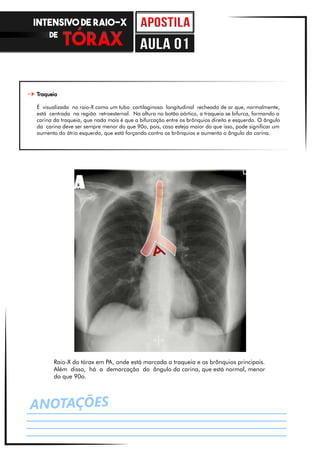

Raio-X do tórax em PA, onde está marcada a traqueia e os brônquios principais.

Além disso, há a demarcação do ângulo da carina, que está normal, menor

do que 90o.

Traqueia

É visualizada no raio-X como um tubo cartilaginoso longitudinal recheado de ar que, normalmente,

está centrada na região retroesternal. Na altura no botão aórtico, a traqueia se bifurca, formando a

carina da traqueia, que nada mais é que a bifurcação entre os brônquios direito e esquerdo. O ângulo

da carina deve ser sempre menor do que 90o, pois, caso esteja maior do que isso, pode significar um

aumento do átrio esquerdo, que está forçando contra os brônquios e aumento o ângulo da carina.